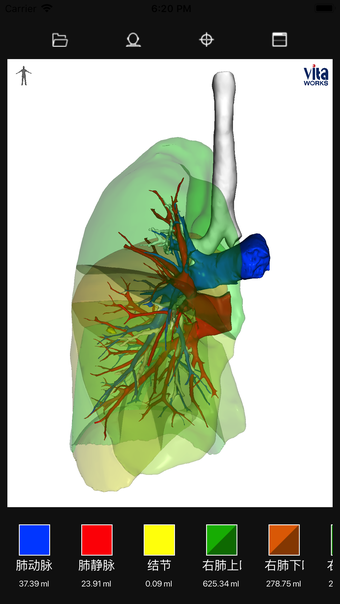

VitaWorks, iPhone için 'Tıp' kategorisine ait ücretsiz bir yazılımdır.iPhone için VitaWorks Hakkında